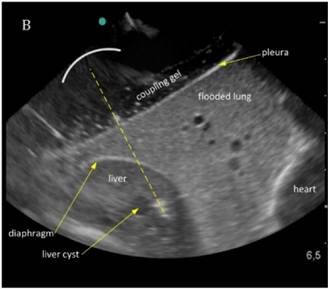

The liver could be examined sonographically trough the flooded lung in all animals. Thereby the lung appeared brighter in echogenity than the liver. In between liver and lung, the diaphragm was visible as an echogenic demarcation (Figure 3A). The flooded lung showed no signs of residual gas content in all animals. Immediately after HIFU insonation a hyperechoic region appeared in B-mode images at the focal position (Figure 3B). Their intensity decreased continuously but remained visible.

Figure 3

Sonographic imaging of the liver through the flooded lung before and after HIFU insonation. A) Transthoracic image shows subcutaneous tissue, pleura, flooded lung and liver. B) Immediately after HIFU insonation a well-demarcated hyperechoic sonolesion occurs in the liver. The yellow dashed line indicates the HIFU beam.